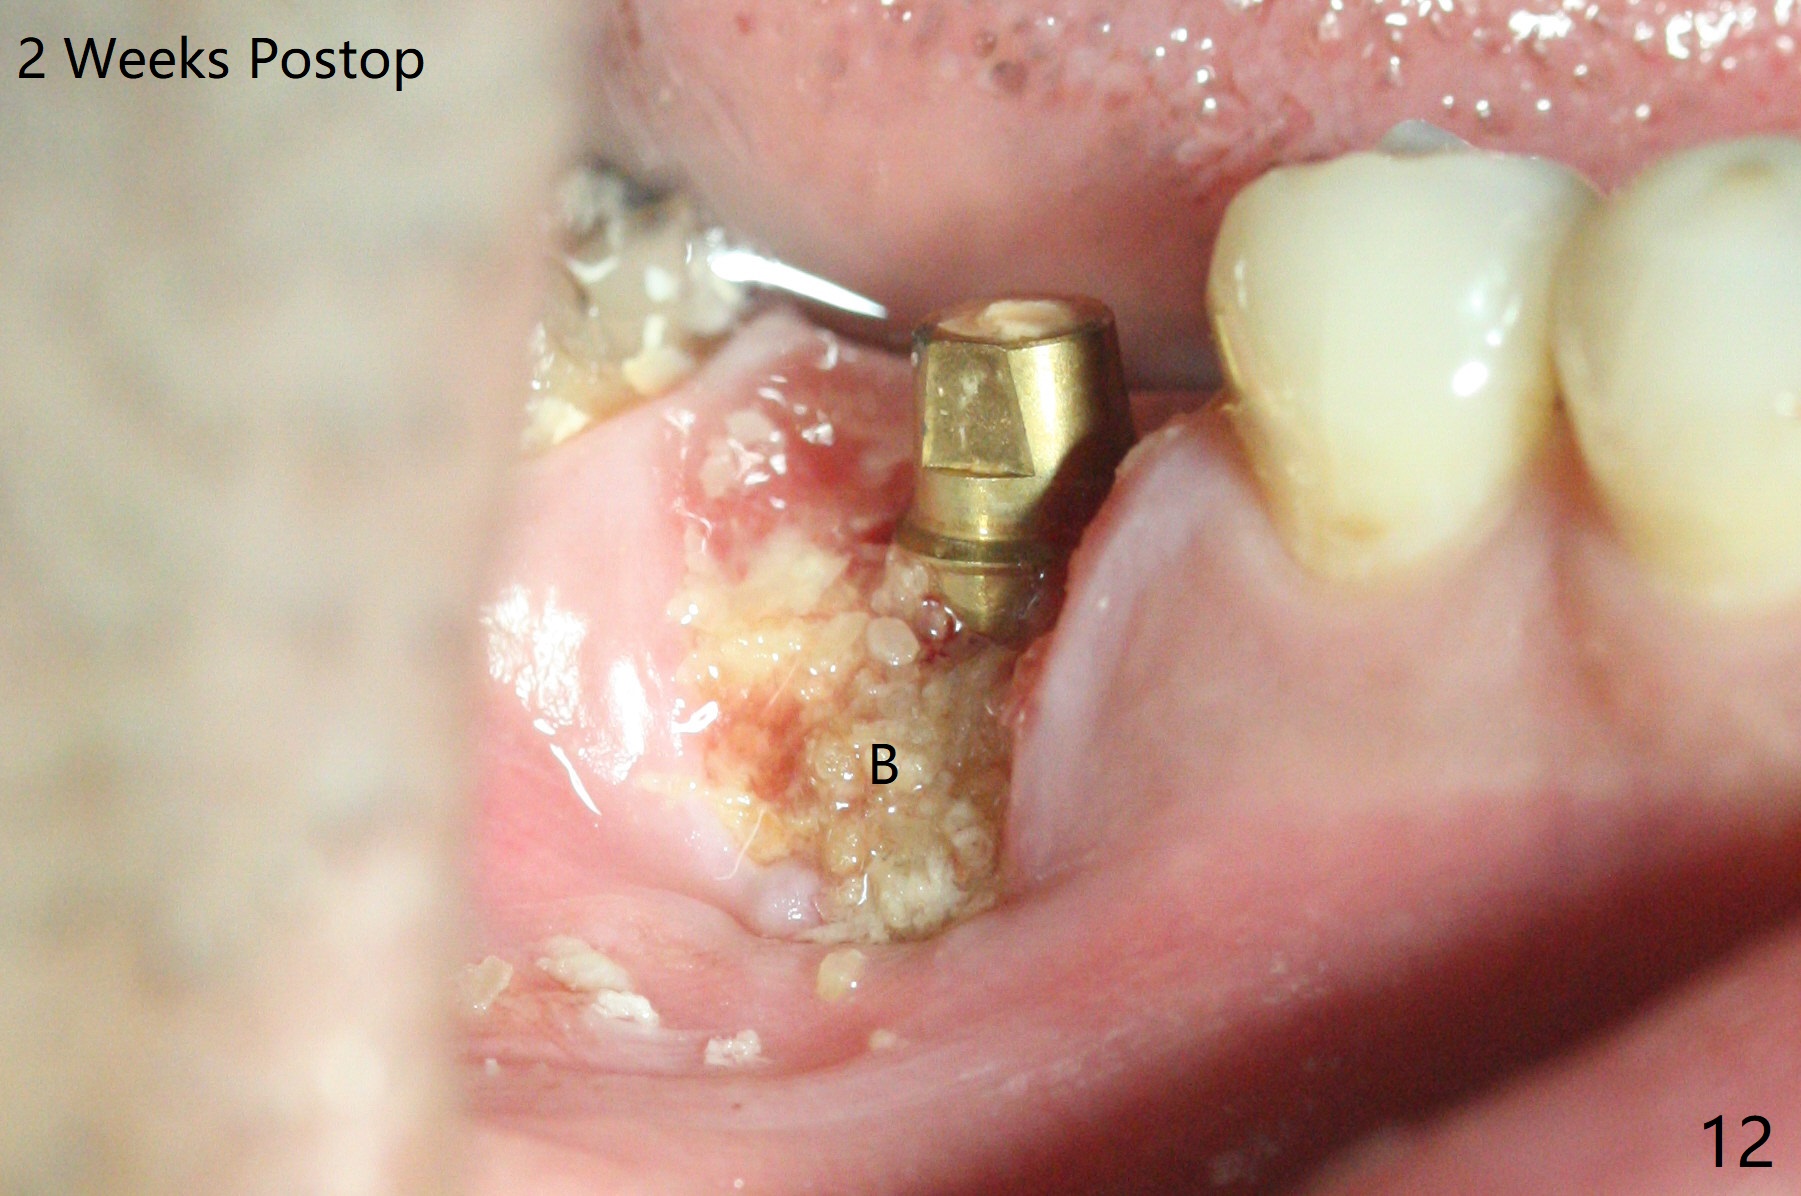

When the tooth #30 is extracted, the gingiva buccal to the septum (S in Fig.1,2 (P: papilla between the mesial and distal roots)) collapses. The latter is fixed with placement of a 4.5x11.5 mm implant (with guide), a 5.2x4(5) mm cemented abutment (Fig.3) and mixture of cortical bone (125μm – 850μm) and cortical/cancellous bone (.5-1 mm) with PRF (sticky bone, B in Fig.4-6). After placement of 2 pieces of PRF membrane over the bone graft, a temporary crown is fabricated to cover the buccal defect (Fig.7 T). Approximately 7.5 mm of the buccal threads are covered by the thick layer of bone graft (Fig.8 B). It is amazing to expect that the bone graft will turn into the buccal plate. It would be better if a narrower implant (4 instead of 4.5 mm) were placed more lingually or there were < 4 mm implant thread exposure (Fig.9). The gingiva reacts to the provisional nicely 7 days postop (Fig.10). The provisional will be removed for modification in 1 month. The patient complains of bad smell from the provisional 2 weeks postop. The provisional is removed. The distal socket (Fig.11 D) is healing, whereas the buccal bone graft (Fig.12 B) seems not have been vascularized. Pedicled flaps (I) should be transferred to cover the buccal bone graft. The margin of the provisional is polished, becomes short, and covered by periodontal dressing, which dislodges 2 days later. One week later, granulation tissue is forming apically with use of oral antibiotic and water jet (Fig.13 *). The bad smell reduces. The superficial loose bone graft changes colar and becomes detached 1 month 10 days postop. The temporary crown with the shortened buccal shelf is reseated for self cleansing or reapplication of PRF if needed (Fig.14).